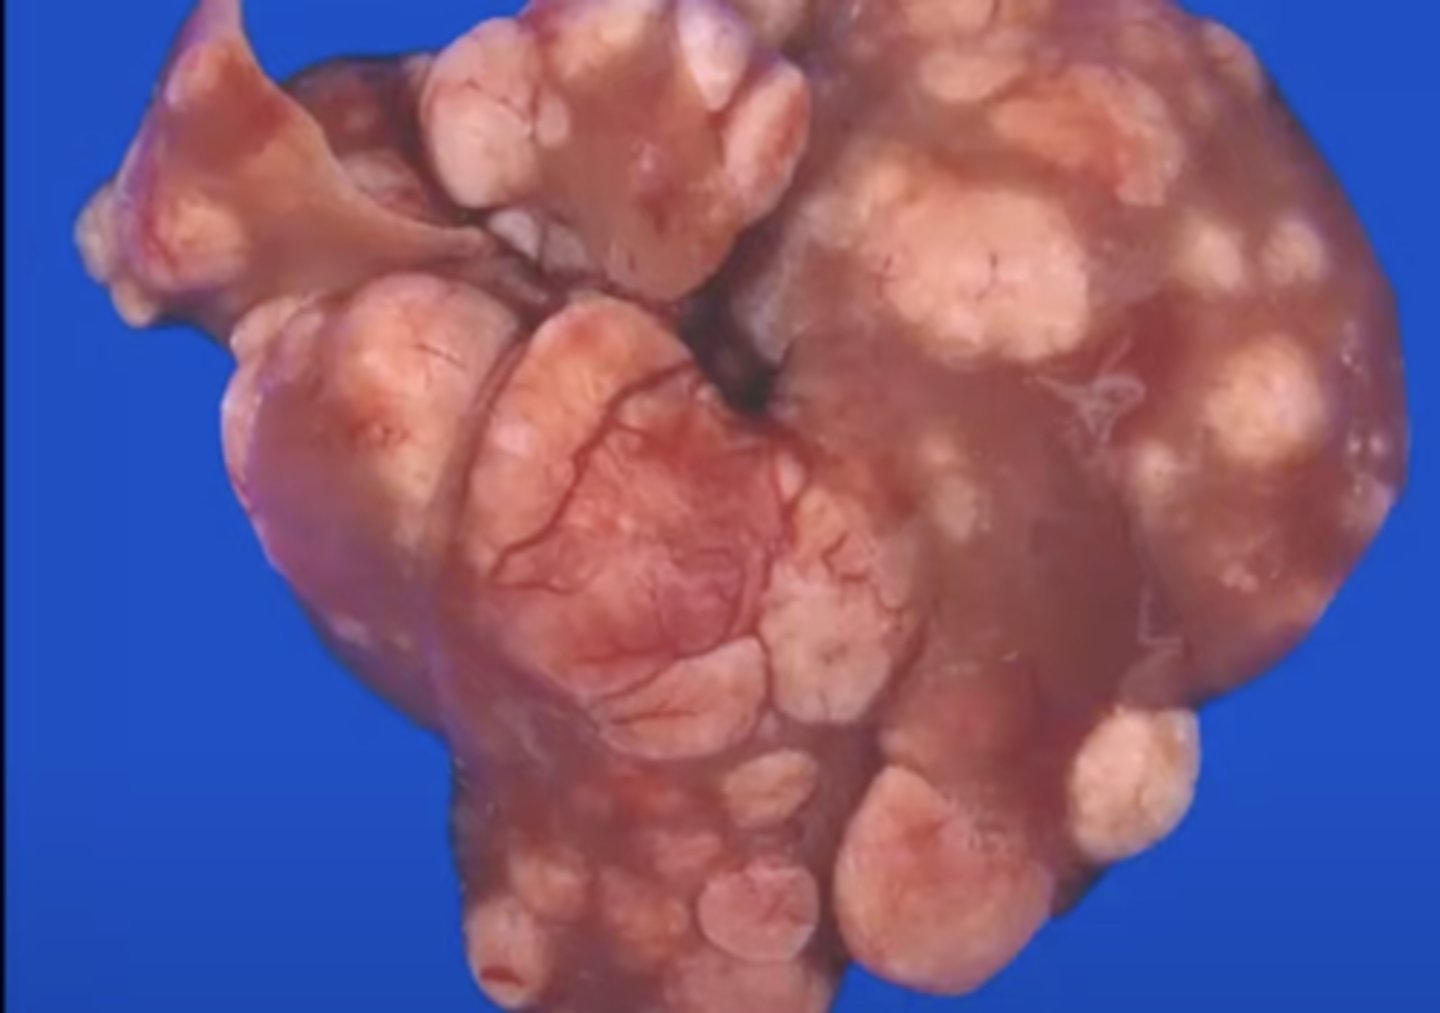

Metastatic tumor

What kind of tumor is this? (broad category)

Hematogenous metastasis

What kind of tumor is this? (broad category)